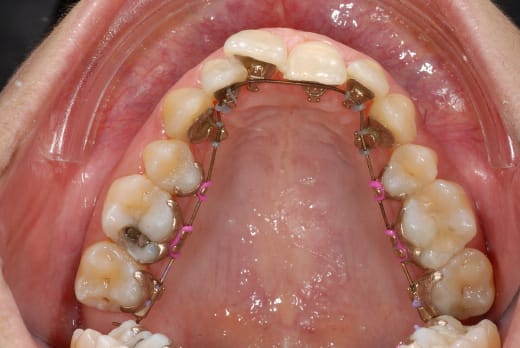

ben voilà des news en photo...

(et que personne me sape le moral...)

Apparemment, ton arc est du twist flex , souple et non traumatisant. Tu vas le garder un bon moment!!!!